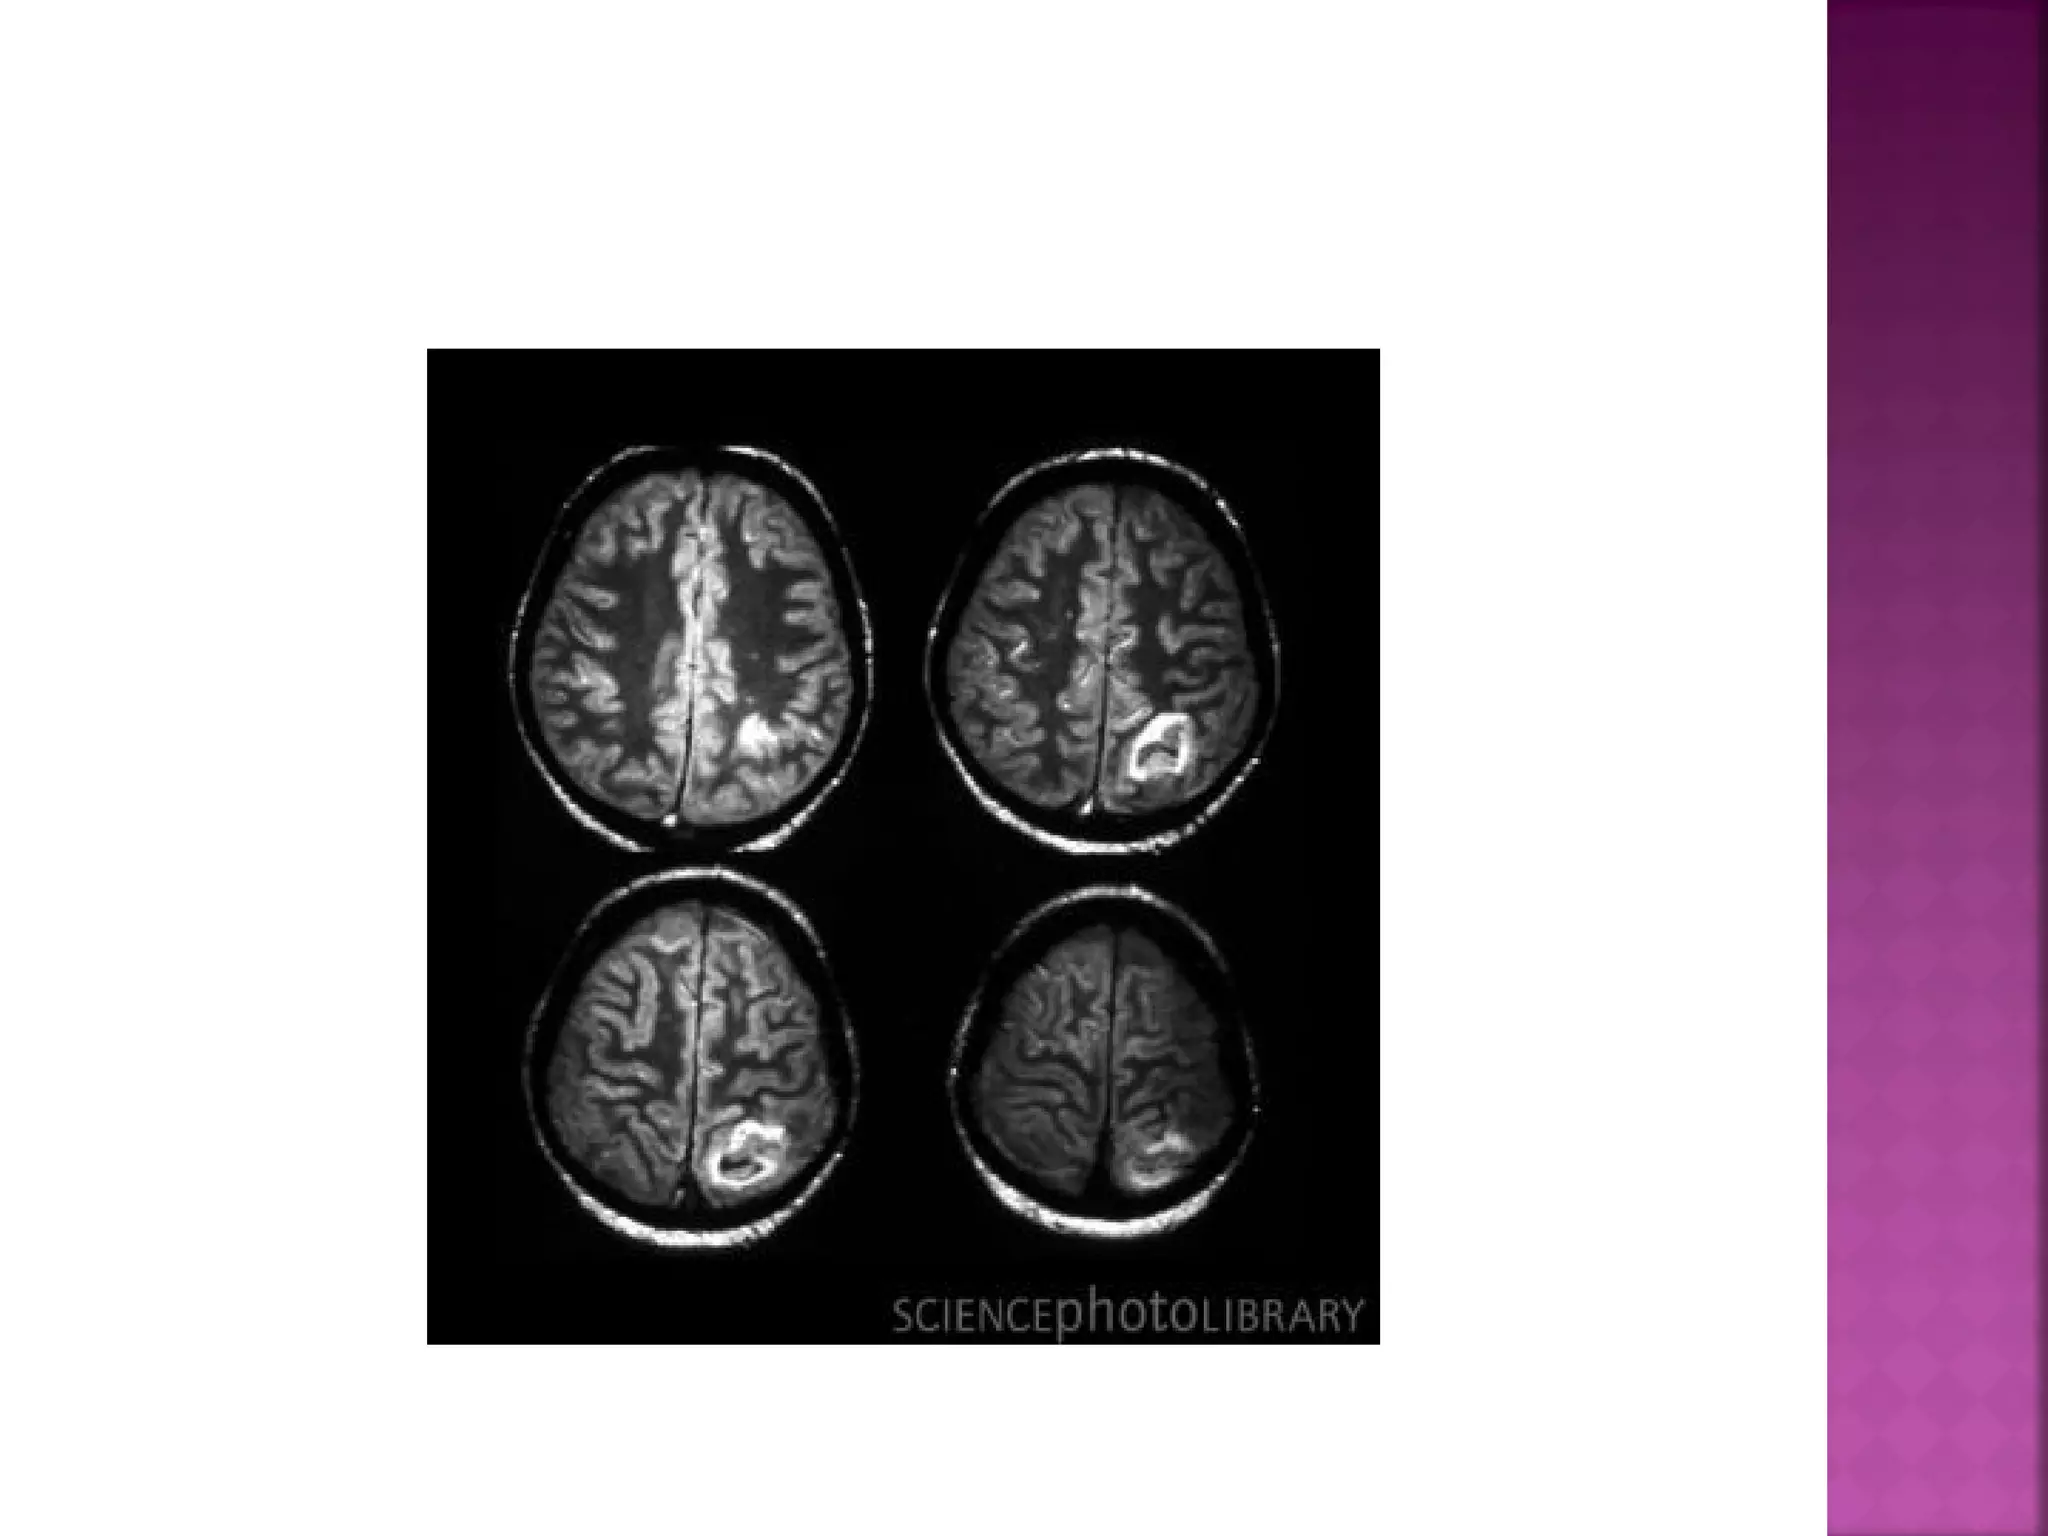

On T2WI and FLAIR infarction is seen as high

SI.

These sequences detect 80% of infarctions

before 24 hours.

They may be negative up to 2-4 hours postictus!

High signal on conventional MR-sequences is

comparable to hypodensity on CT.

It is the result of irreversible injury with cell

death.

So hyperintensity means BAD news: dead

brain.

In the acute phase T2WI will be normal, but

in time the infarcted area will become

hyperintense.

The hyperintensity on T2WI reaches its

maximum between 7 and 30 days. After this

it starts to fade

 On T2WI andFLAIR infarction is seen as high SI. These sequences detect 80% of infarctions before 24 hours. They may be negative up to 2-4 hours postictus!

 High signal onconventional MR-sequences is comparable to hypodensity on CT. It is the result of irreversible injury with cell death. So hyperintensity means BAD news: dead brain.

  In the acutephase T2WI will be normal, but in time the infarcted area will become hyperintense. The hyperintensity on T2WI reaches its maximum between 7 and 30 days. After this it starts to fade